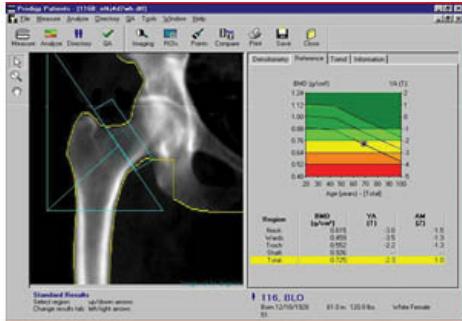

DEXA Scan

Overview

- Bone Mineral Density (BMD) measurement

- DEXA: Dual Energy X-ray Absorptiometry

- Primary sites: Spine / neck of femur

WHO Classification of BMD Using DEXA Scan

Note: T-score represents the number of standard deviations (SD) a patient is above or below the mean BMD of a young adult.